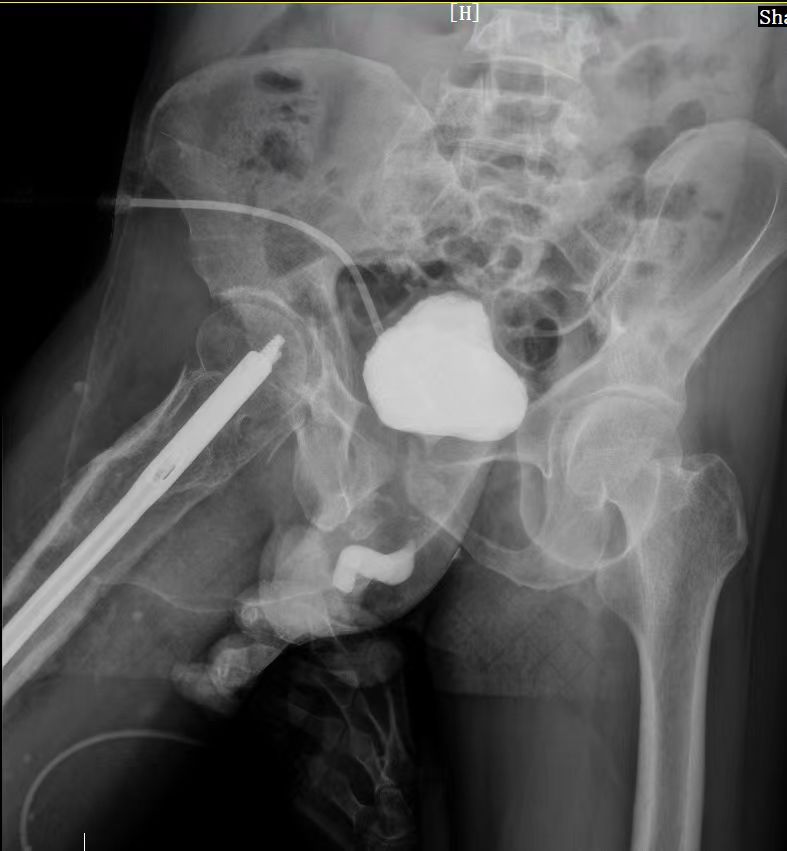

西咸院区移植泌尿外科。经科室大讨论,科室主任李智斌团队迅速制定治疗策略,行尿道造影检查可见尿道完全断裂,遂决定行尿道重建术+尿道狭窄瘢痕切除术。